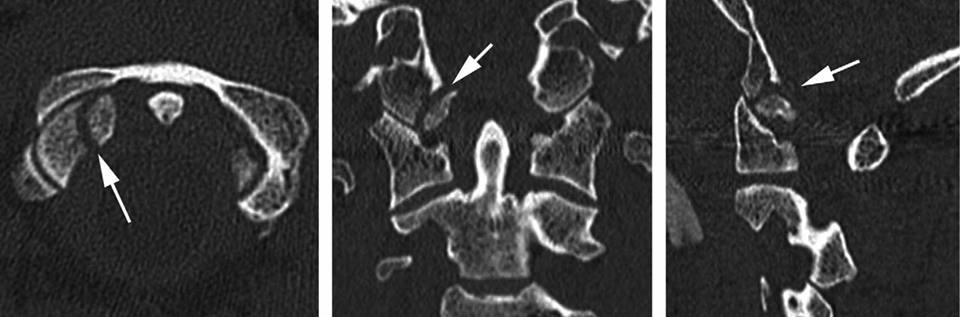

46歲男性單車手倒下導致頭顱枕骨髁骨骨折和頸椎C1-2韌帶損傷

他的頭顱和頸脊柱都不穩定, 由於頸椎神經損傷引起的手臂暫時性麻木

像前幾天86歲的老婆婆病人類似, 相同的腦神經外科醫生團隊,類似的手術,但這次涉及後頭顱枕骨要在他枕頭部位的頭骨上鉗入鋼片, 存在風險會損害他的小腦和主要靜脈血管竇 , 可引致中風或死亡.